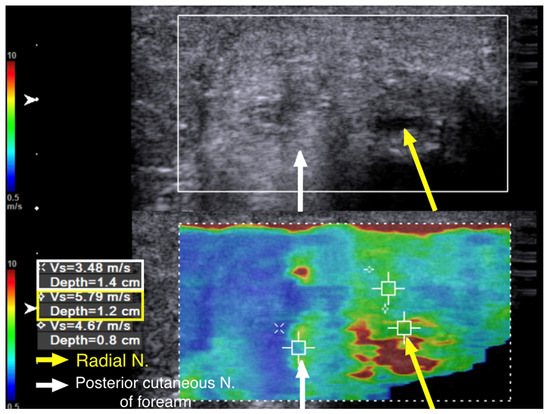

Three months later, the neuropathic pain was completely resolved, the muscle power of the ECRL and EDC had increased to 4+ (near normal), and the EIP had increased to 4; the neurodiagnostic study showed reinnervation over the EIP as well. The SWE revealed a further decrease in the hardness to 4.67 m/s at the previous entrapment site at the entrance to the spiral groove (Figure 4, yellow box). No further treatment was required, and the patient had regained full motor function with no numbness at the last follow-up 21 months after the hydrodissection.

Figure 4. Case 1: Shear wave velocity nine months after hydrodissection. Shear wave velocity (SWV) investigation of the radial nerve (long axis) over the spiral groove. Nine months after the first hydrodissection, the hardness of the nerve has returned to near normal, with a shear wave velocity of 4.67 m/s. Yellow arrow and box: radial nerve in longitudinal view; white arrow: bony cortex of humerus.